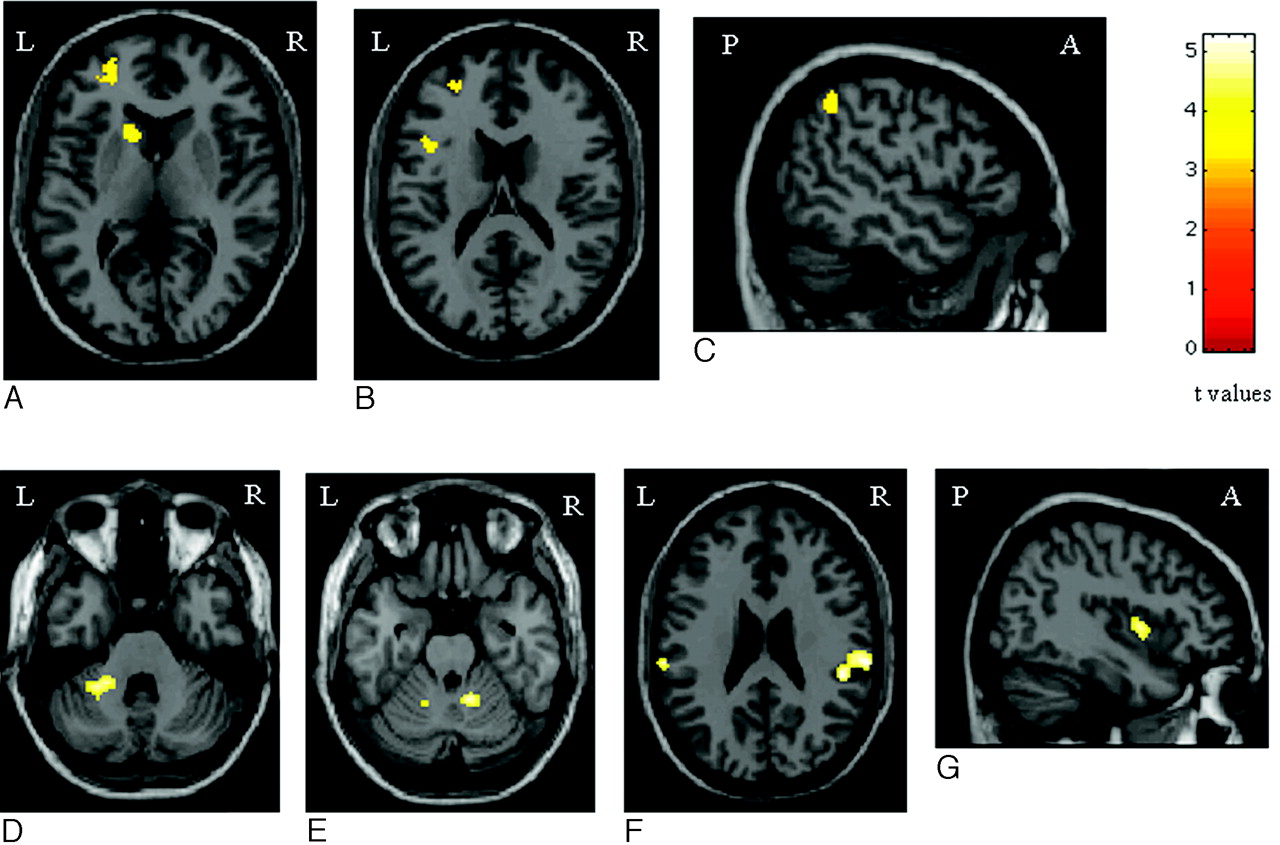

Compared with patients who were CI, patients who were CP had more significant activations of the head of the left caudate nucleus (SPM coordinates: −12, 14, 6), the left PFC (SPM coordinates: −26, 54, −6; and −42, 12, 18), and the left inferior parietal lobule (Brodmann area 40) (SPM coordinates: −50, −50, 50) (Fig 3). Conversely, compared with patients who were CP, those with CI had more significant activations of the SII bilaterally (SPM coordinates: 50, −34, 24; and −62, −26, 24), the cerebellum bilaterally (SPM coordinates: 14, −50, −24; and −26, −44, −32; and −14, −54, −24), and the right insula (SPM coordinates: 40, 4, 2) (Fig 3).

Areas of increased activations in patients with PPMS without cognitive impairment vs. those with cognitive impairment (A−C), and areas of increased activations in patients with PPMS with cognitive impairment vs. those without (D−G) during the analysis of the 2-back task (random-effects analysis, ANOVA, P < .05 corrected for multiple comparisons). Note that the color-encoded activations have been superimposed on a rendered brain and normalized into the standard SPM space (neurologic convention). See text for further details.